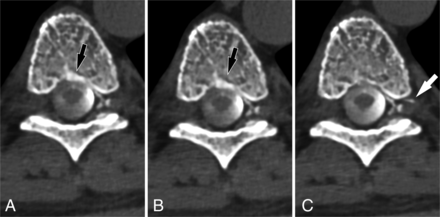

A right T9 CVF best visualized during resisted inspiration. Axial MIP images from CTM performed on a patient with SIH are shown during maximum suspended inspiration (A), resisted inspiration (B), and the Valsalva maneuver (C). Drainage of the CVF into a segmental vein (arrow) is best seen during resisted inspiration.

A left T3 CVF best visualized during the Valsalva maneuver. Axial MIP images from CTM performed on a patient with SIH are shown during maximum suspended inspiration (A), resisted inspiration (B), and the Valsalva maneuver (C). The CVF originating at the T3 level on the left (arrow) is best visualized during the Valsalva maneuver. The presence of a CVF was suspected on the basis of faint hyperdensity in the same location on the initial maximum suspended inspiration image.